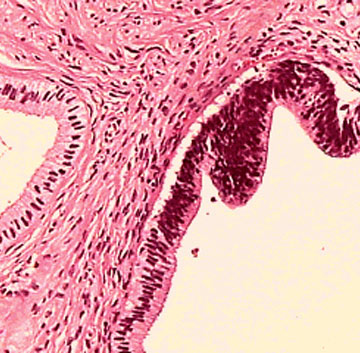

Exame de Biópsia

A biópsia é um exame que consiste na retirada de um fragmento de uma parte do corpo (biópsia incisional) ou mesmo de um órgão ou lesão como um todo (biópsia excisional). Na maioria das vezes, quando usamos o termo “biópsia”, estamos nos referindo a biópsia incisional. A biópsia não é feita apenas para investigação de câncer, mas também pode ser usada em outras situações como, por exemplo, durante a endoscopia com biópsia digestiva alta. Nesse procedimento muitas vezes é retirado um fragmento da mucosa do estômago para investigar se há gastrite e também é feita a pesquisa de uma bactéria causadora de gastrite, chamada Helicobacter Pylori. Com este resultado, o seu médico irá estabelecer o melhor tratamento medicamentoso para erradicar a bactéria que causa gastrite, se este for o seu caso.